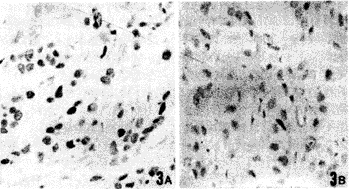

对52例乳腺癌石蜡切片分别用自制单抗M126和进口单抗PAB1801与P53反应,阳性率分别为42.3%(22/52)和48.1%(25/52)。阳性显色均为细胞核棕黄色颗粒状着色,癌细胞着色显示出异质性。其中有3例用进口单抗PAB1801细胞没有着色,而用自制单抗M126却显示细胞核阳性着色。用进口单抗PAB1801时石蜡切片经抗原修复后着色强度和面积均有不同程度的提高,而用自制单抗M126石蜡切片不经抗原修复也得到很好的结果。自制单抗M126和进口单抗PAB1801对乳腺癌冰冻切片,膀胱癌石蜡切片均显示了癌细胞核的阳性着色,两者的阴阳符合率基本吻合(乳腺癌冰冻切片阳性率分别为M126 45%(9/20),PAB1801 40%(8/20);膀胱癌石蜡切片阳率性分别为M126 37.5%(3/8),PAB1801 37.5%(3/8)。图3中A、B分别为自制单抗M126和进口单抗PAB1801对同一块乳腺癌石蜡切片的IHC染色结果。

图3 人乳腺癌石蜡切片P53免疫组织化学分析 ×500

A和B分别用单抗M126、McAb PAB1801作为一抗

Fig.2 IHC of P53 on paraffin sections from human breast cancer.×500

The stainings were performed by SP and counterstained using hematoxylin,A and B were stained with McAb M126and McAb PAB1801,respectively.